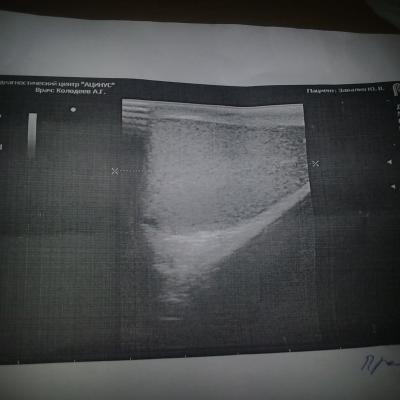

Нечитаемый текст.